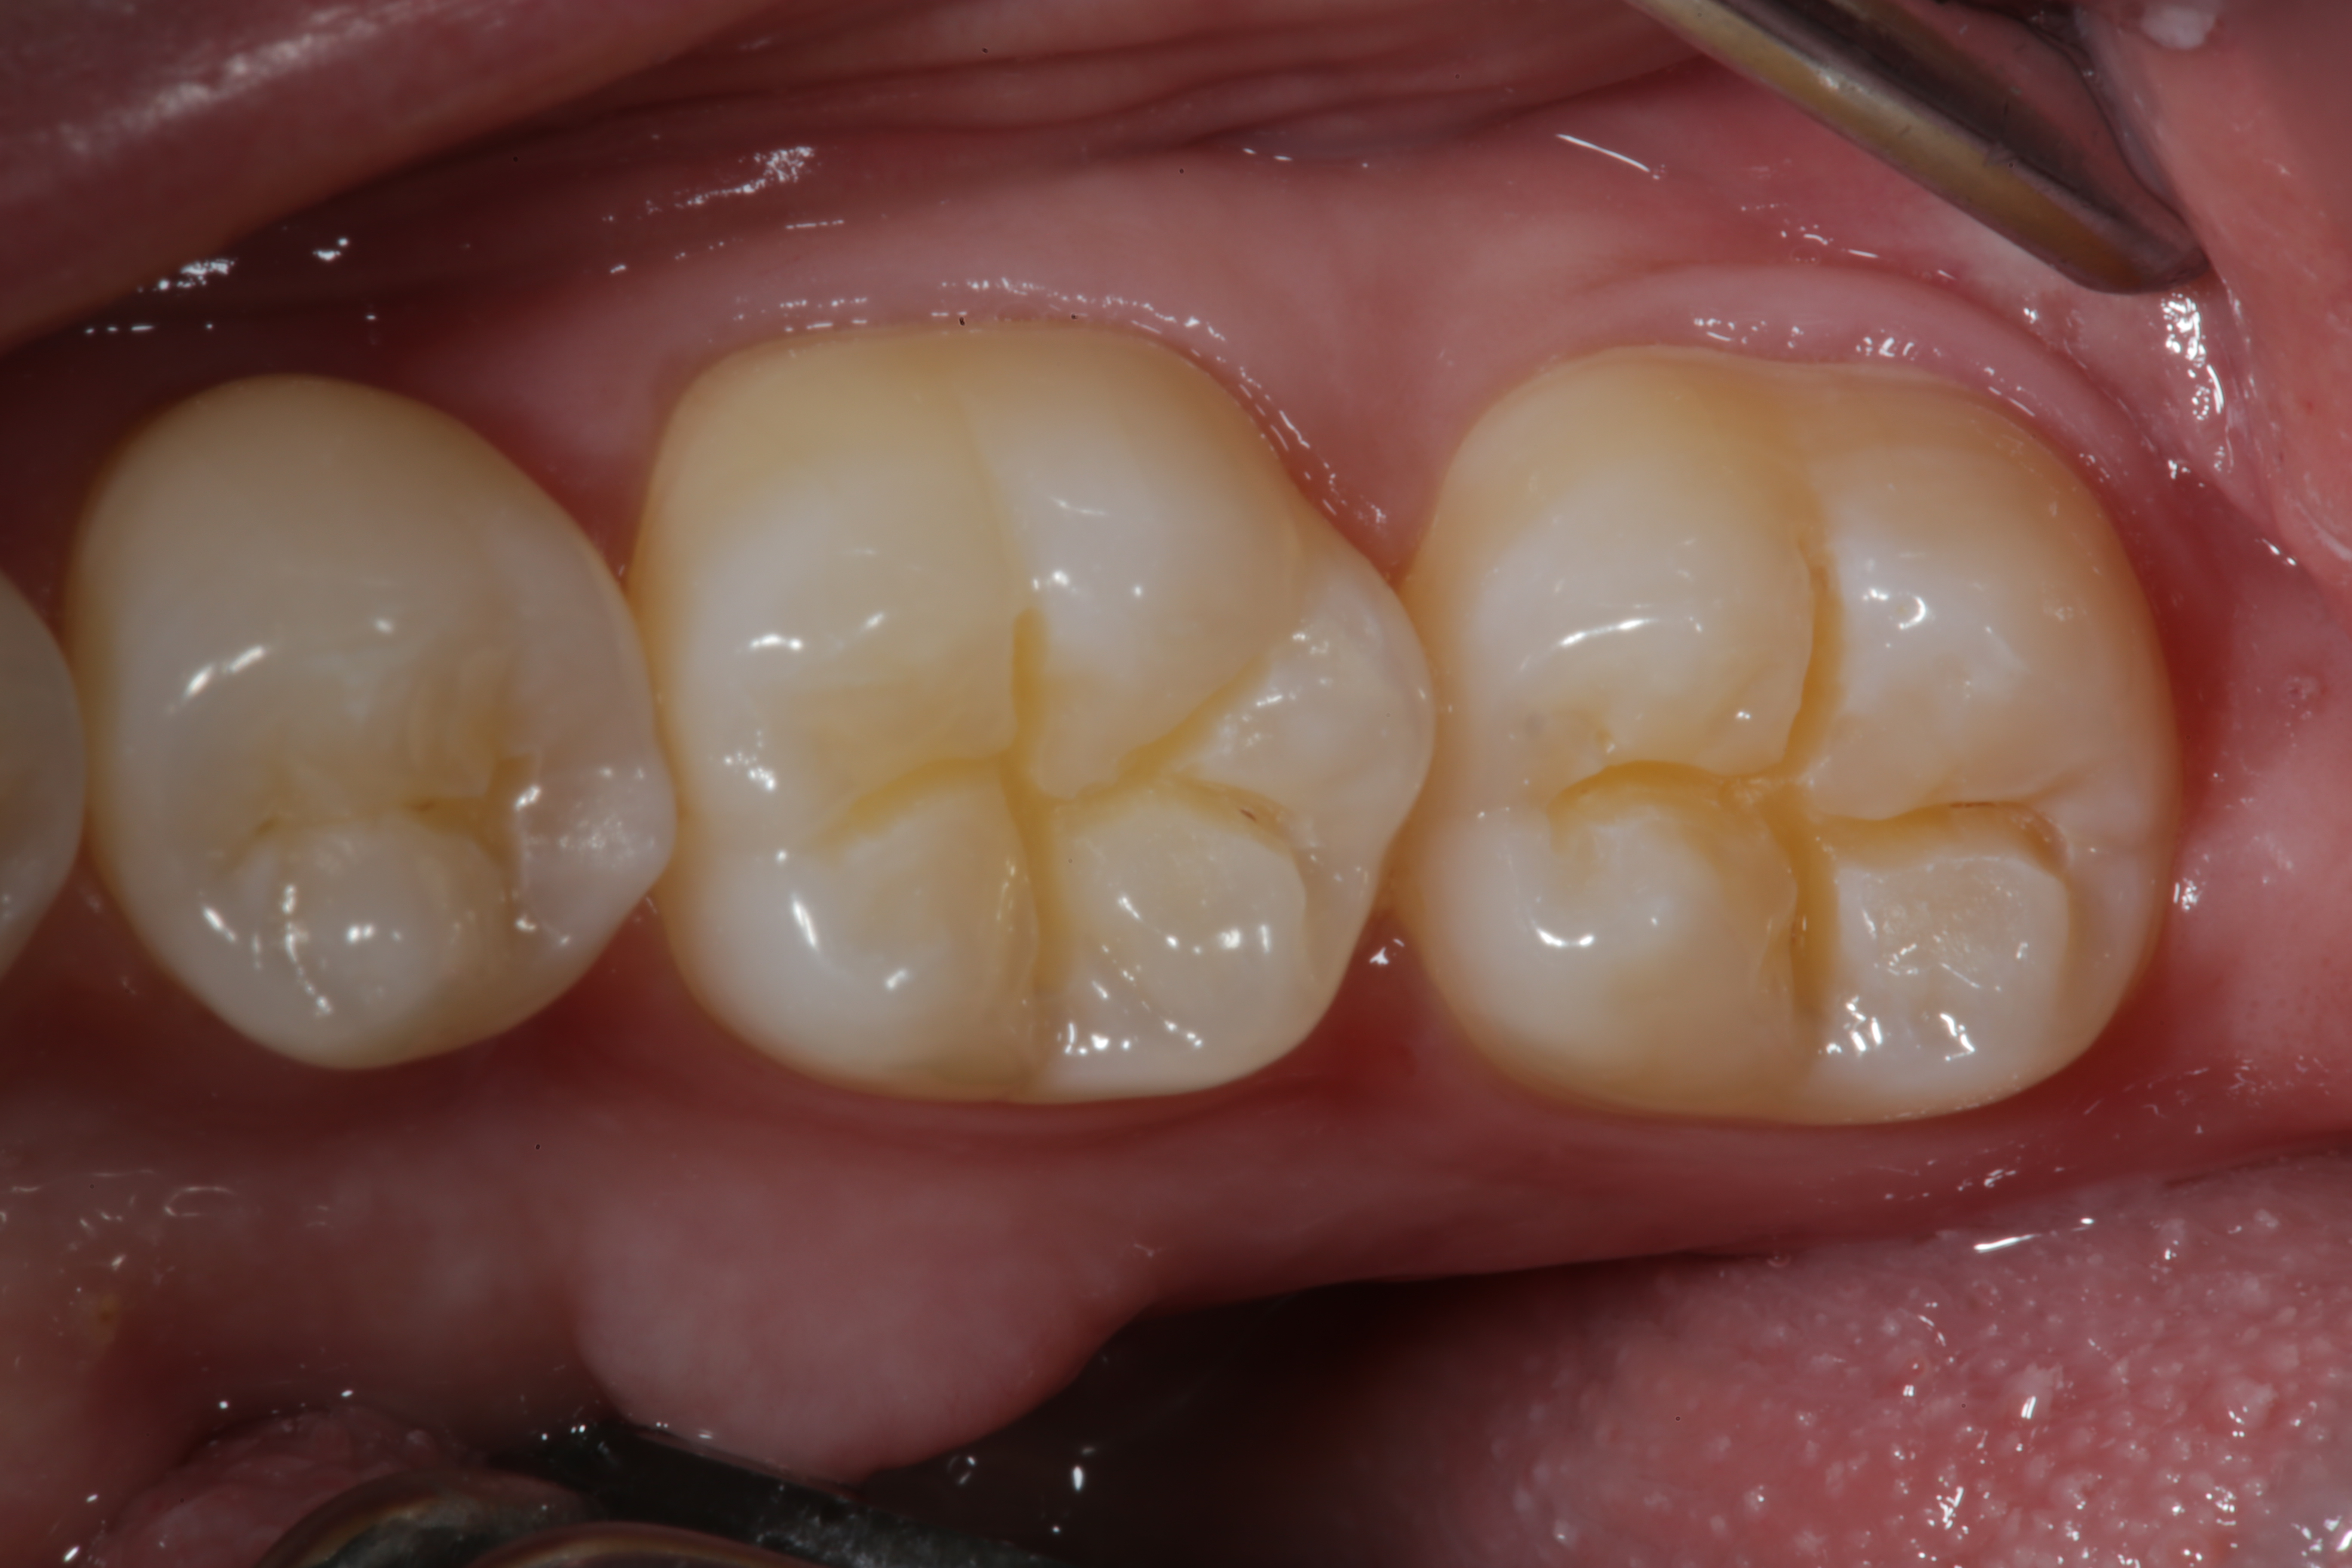

Fig 25. An occlusal view of the completed Giomer bulk-filled composite restorations on teeth Nos. 29 and 30.

Figure 25